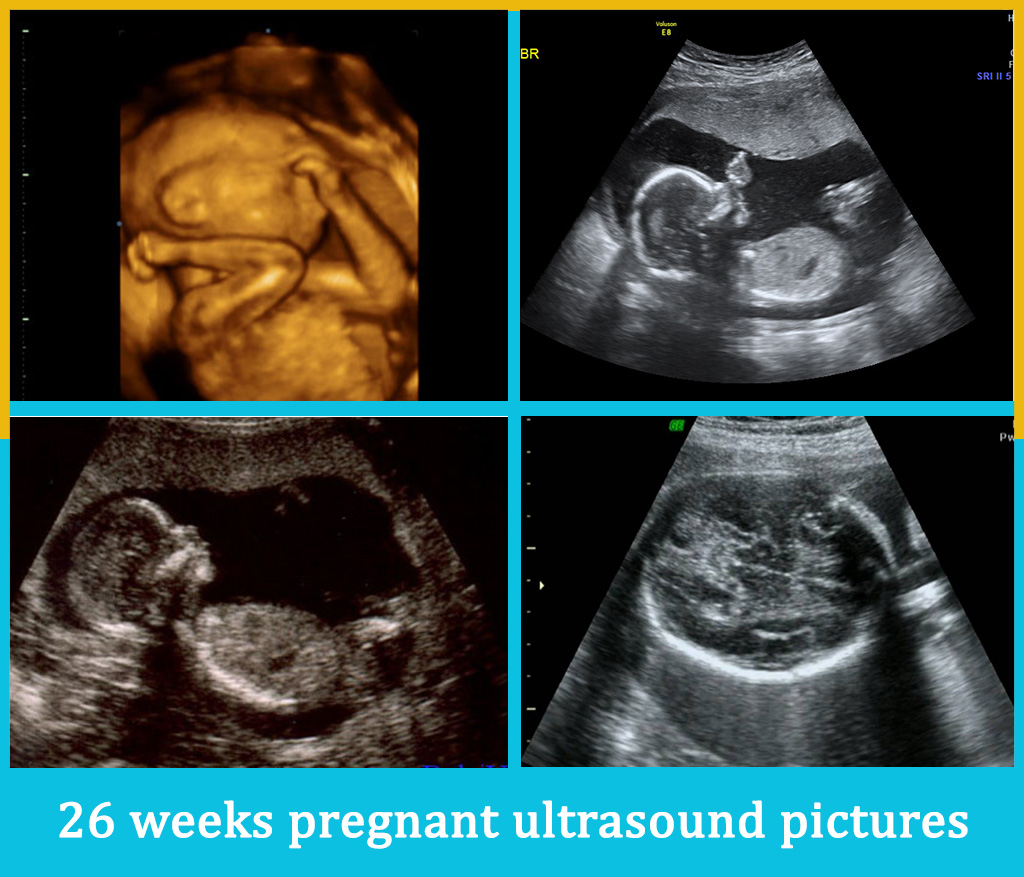

Normal 26 week pregnancy and ultrasound, the useful guide.

Normal 26 week pregnancy and ultrasound, the useful guide.

26 Weeks Pregnant – Second Trimester – Ultrasound Gallery

Mommy in the Making : Wordless Wednesday: Ultrasound pics!

Pregnancy Ultrasound Safety – Rivon

Week-by-week pregnancy (weeks 14-26)